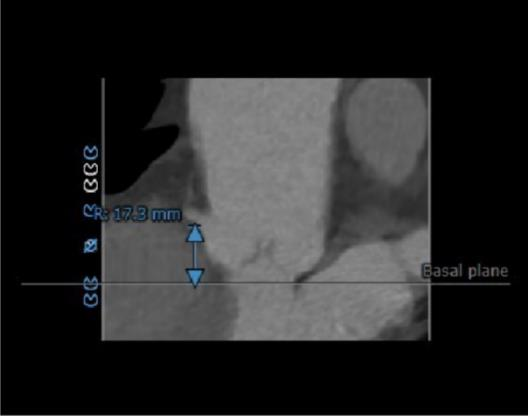

右冠开口高度17.3mm

RIGHT CORONARY